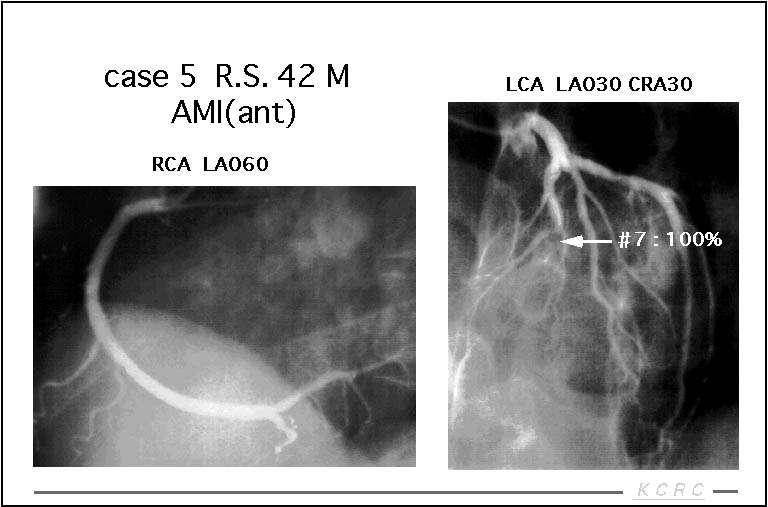

【スライド15】

他の核種を用いた症例を示します。前壁の急性心筋梗塞の症例です。冠動脈造影ではLADに完全閉塞を認めます。